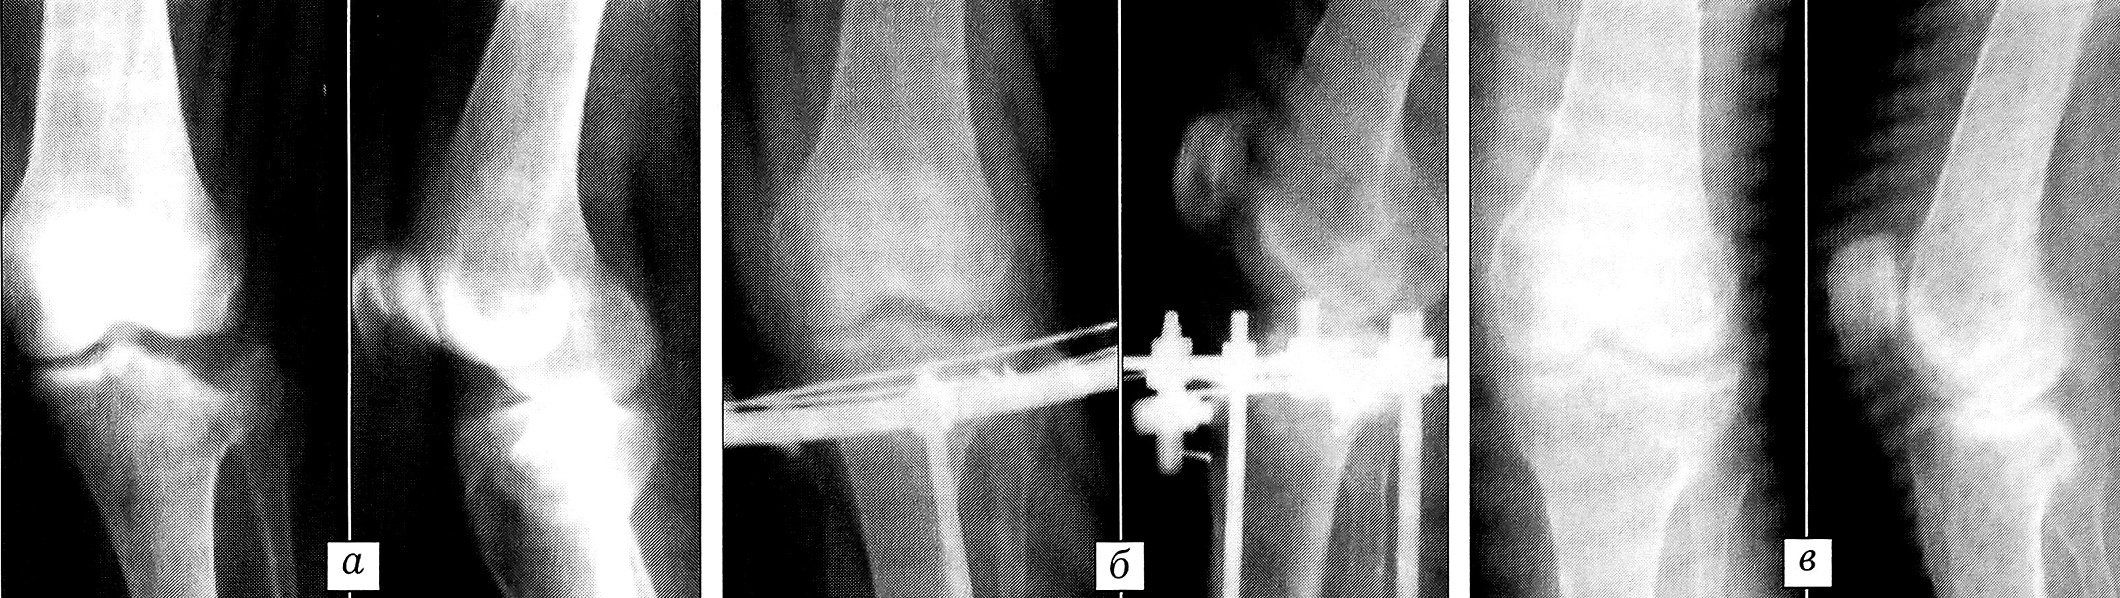

При полных и неполных оскольчатых внутрисуставных переломах мыщелков с большой степенью компрессии и смещения (В2, ВЗ, СЗ), а также при неудаче «полуоткрытой» репозиции переломов В2, С2 применялась открытая репозиция или «щадящая» артротомия. Под жгутом по наружной поверхности коленного сустава делали дугообразный или Z-образный разрез длиной 8-10 см. Сустав вскрывали под мениском, который отводили вверх с помощью держалки. После этого хорошо выявлялся характер смещения отломков, становился возможным визуальный контроль репозиции. При плохом качестве кости производили пластику дефекта губчатой кости свободным аутотрансплантатом из мыщелка бедра или гребня подвздошной кости. В последнее время мы предпочитаем брать аутотрансплантат из мыщелка бедренной кости со стороны повреждения, так как при этом не требуется дополнительного разреза, а лишь незначительно увеличивается основной. Объем забираемой губчатой кости является достаточным для восполнения дефекта компримированного мыщелка большеберцовой кости. Осложнений, связанных с применением данной методики, мы не наблюдали. После устранения смещения отломков и восстановления конгруэнтности суставной поверхности через плоскость излома, большей частью чрескожно, проводили 2—3 спицы с упорными площадками и 1~2 гладкие спицы, в средней трети большеберцовой кости проводили 2 гладкие спицы. Проведение спиц в верхней трети голени приближенно к фронтальной плоскости позволяло использовать дуги без снижения стабильности. Монтировали аппарат Илизарова из двух опор (рис. 4). После рентгенологического контроля репозиции рану ушивали. Со 2-3-го дня пациентов активизировали, начинали разработку движений в коленном суставе, назначали упражнения на укрепление четырехглавой мышцы бедра. Дозированную нагрузку на оперированную конечность разрешали со 2-3-й недели после операции. Средний срок фиксации в аппарате составлял 6-10 нед (рис. 5).

Рис. 5. Рентгенограммы больной 57 лет с переломом наружного мыщелка большеберцовой кости типа ВЗ.a — до операции; б — после открытой репозиции и фиксации в аппарате из двух дуговых опор; в — через 3 года после операции.